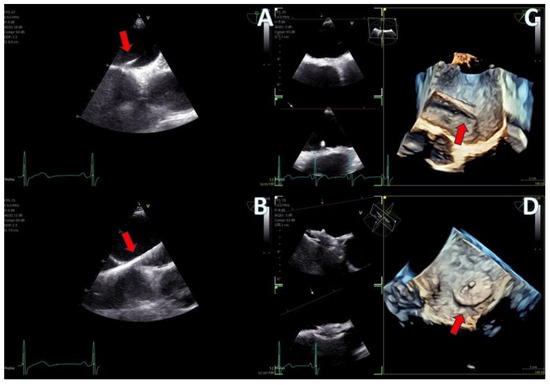

Regarding imaging quality, almost all patients exhibited excellent images without any compromise in resolution, obviating the need to confirm findings using the standard TEE probe (Figure 3 and Figure 4, video S5). Despite the one patient requiring additional sedation due to intense pharyngeal reflex, the quality of images obtained remained consistent across all cases. In 22 cases out of 30 included in this study, the 2D and 3D imaging quality received a score of 5 suggesting excellent imaging totally equal to the one acquired with the adult probe. In four cases, 2D and 3D images were commented as good with a score of 4 and in another four cases, while the 2D images were excellent, 3D images were again mentioned to be good, almost equal to the standard probe but not exceptional enough to receive a grade of 5 (Table 3).

Figure 3.

Dual crop 3D volume-rendered atrial (left) and ventricular (right) views of normal mitral valve.

Figure 4.

(A) A 4D demonstration of a true−bicuspid aortic valve (red arrow), (B) Biplane 2D demonstration of a true−bicuspid aortic valve (red arrow), (C) Chronic dissection of descending aorta (red arrow showing the wall of the true lumen), (D) 3D volume-rendered color Doppler image showing the true (right arrow) and the false lumen (left arrow).